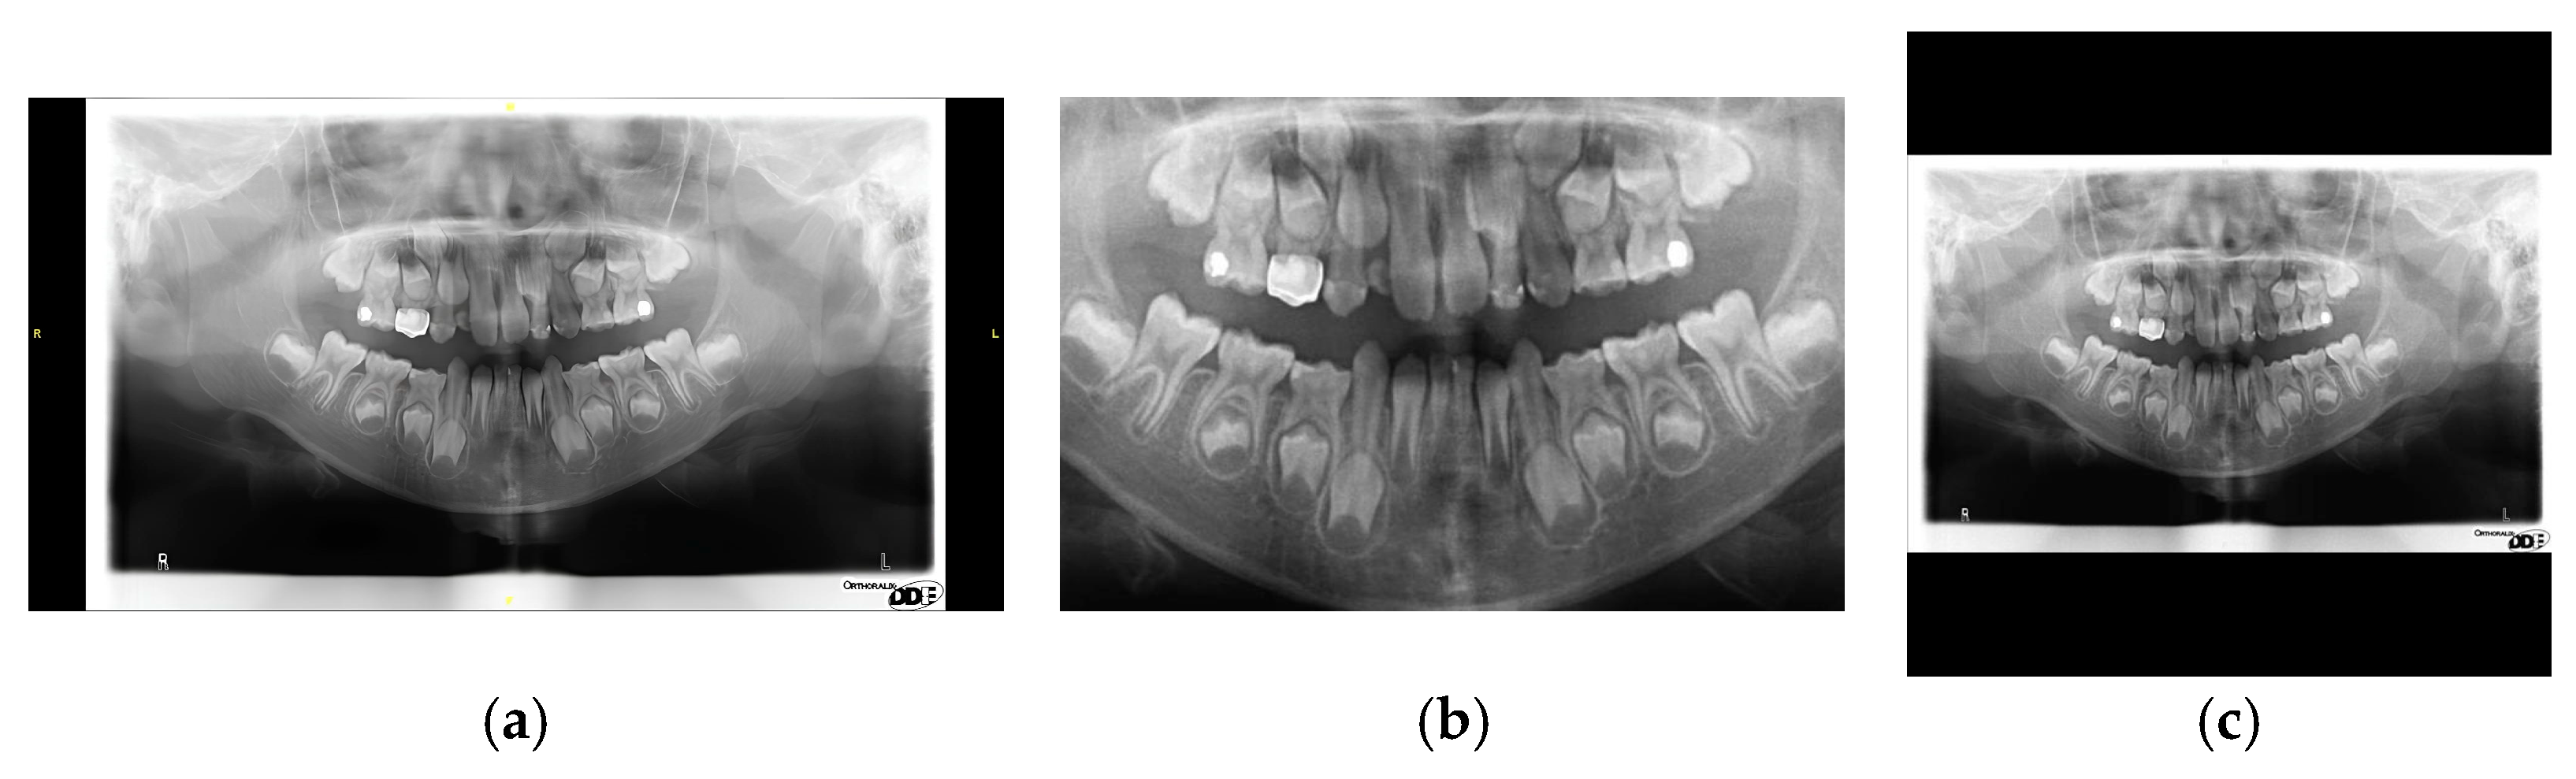

| Cutting Black Borders + Padding | Sharpening + Median Filtering | |

|---|---|---|

| Precision ↑ | 95.07 | 98.16 |

| Recall ↑ | 97.86 | 98.44 |

| mAP50 ↑ | 98.22 | 98.48 |

| mAP50~95 ↑ | 70.18 | 72.94 |

| F1-score ↑ | 96.44 | 98.30 |

| Image | ![]() | ![]() |